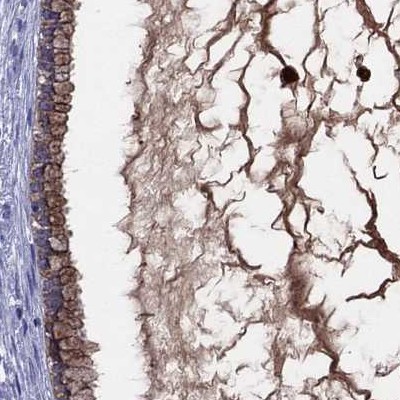

Immunohistochemical staining of human cerebral cortex, cervix, uterine, colon and liver using Anti-SERPINA3 antibody HPA002560 (A) shows similar protein distribution across tissues to independent antibody HPA000893 (B).